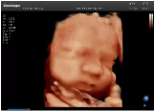

4容積探頭

積探頭是在二維圖像的基礎(chǔ)上,將連續(xù)采集的空間分布位置,經(jīng)過(guò)計(jì)算機(jī)重建算法,從而獲得完整的空間形態(tài)。

適用于:胎兒面部、脊柱和肢體等。

優(yōu)勢(shì)特點(diǎn):快速獲取、掃查連續(xù)均勻、解剖結(jié)構(gòu)顯示為容積數(shù)據(jù)、準(zhǔn)確進(jìn)行容積測(cè)量。